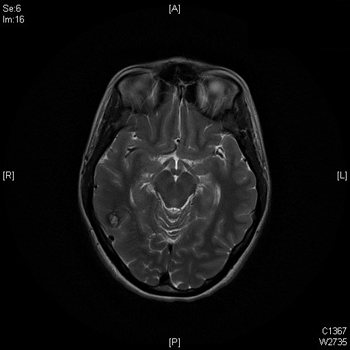

C’est une initiative originale. Pour la toute première fois, le centre hospitalier américain Memorial Hermann va décrire en temps réel sur Twitter (@houstonhospital) le déroulement d’une opération neurochirurgicale consistant à ablatir un hémangiome caverneux situé dans le lobe temporal d’un patient. Les commentaires sont accompagnés de photographies publiées sur Pinterest et sur Twitpic.

L’opération, qui a débuté aux alentours de 14h30 (heure française) doit durer en tout quatre heures : trois heures pour l’intervention à proprement parler et une heure pour la phase de réveil suite à l’anesthésie générale. Mais le compte Twitter de l’hôpital a commencé bien avant la première incision à publier des messages explicatifs.

Bien entendu, ce n’est pas Dong Kim qui s’occupe de live-tweeter l’opération. C’est un spécialiste des tumeurs cérébrales, le docteur Scott Shepard, qui s’en charge, dans une pièce attenante. C’est lui qui commente les différentes étapes de l’opération et répond aux interrogations des internautes, à l’image d’une question sur les caractéristiques de l’hémangiome caverneux (taille et masse).